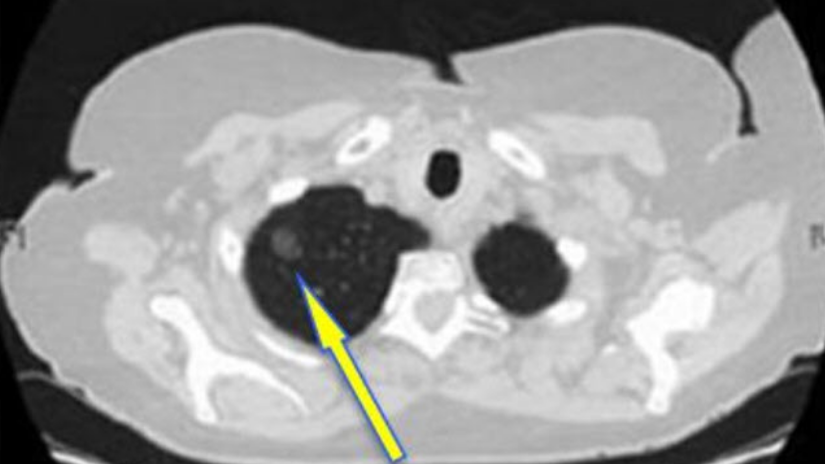

● 恶性结节

普遍长得比较嚣张且颜值低:有分叶、毛刺,分界不清,供血丰富。

这种结节看起来就像个刺头,一点都不老实,模糊分界是因为想往正常肺组织里扩张捣乱又不想太高调,丰富的供血可以悄咪咪地吸收周围组织营养让自己迅速生长。

不同密度、不同大小的肺结节恶性概率不一样,根据恶性程度排序:部分实性结节>纯磨玻璃结节>实性结节,但并不是绝对就有恶变的可能。